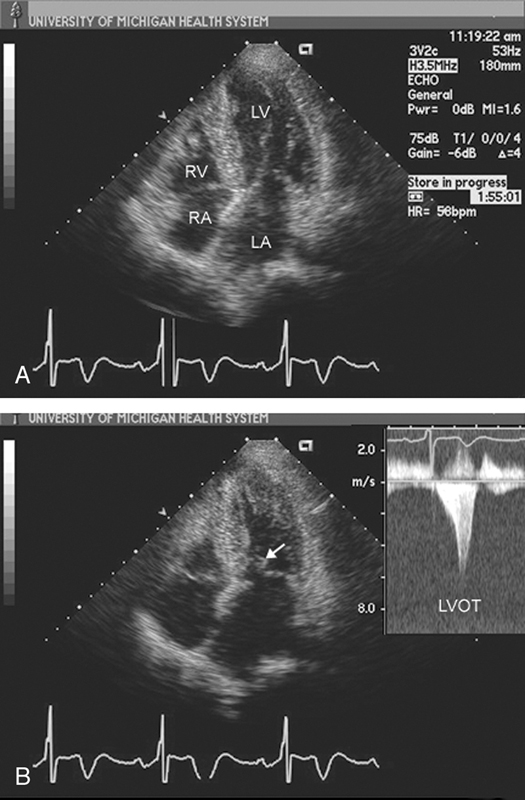

فحوصات تشخيصية لبعض امراض القلب والشرايين التاجية